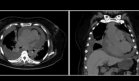

A los 90 días de vida, desarrolló un aumento del diámetro cervical lateral izquierdo, con irradiación a la hemiface izquierda, distensión yugular, cianosis central y taquipnea. Se sospechó síndrome de vena cava superior (SVCS), por lo que se retiró el catéter venoso central.

La ecografía Doppler reveló trombosis de la vena cava superior sin afectación de la unión de las venas yugular y subclavia en la aurícula derecha. Se inició anticoagulación con heparina de bajo peso molecular debido al riesgo de tromboembolismo pulmonar paradójico por foramen oval permeable.

Dado que no se observó mejoría con el tratamiento inicial, se realizó una reunión interdisciplinaria que determinó la necesidad de cavografía y flebografía, seguidas de trombectomía mecánica, trombolisis con alteplasa y angioplastia de la vena cava superior.